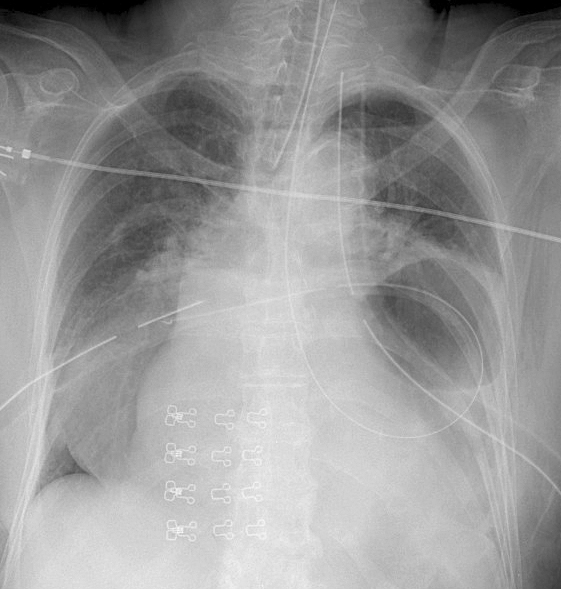

Gallery Mediastinum Hiatus Hernia Hiatus Hernia Case 3 (see CT)

Hiatus Hernia

Case  3 (see CT)